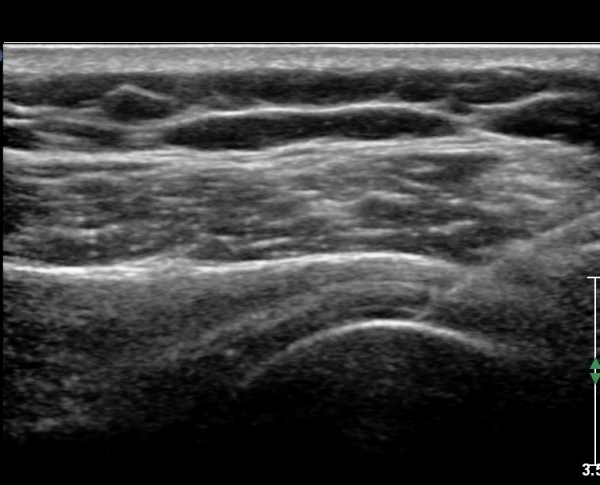

ŽÃËÀÚ¸¦ Á¶±Ý ¸»´ÜÀ¸·Î À̵¿ÇÏ´Ï ¿À±¸µ¹±â°ßºÀÀÎ´ë °ßºÀ ºÎÂøºÎ °ñ±ØÀÌ °üÂûµÇ°í ÀÎ´ë ½ÉÃþºÎ¿¡ ¼ö¾×Àú·ù°¡ ÀÖ¾î ¸¸¼ºÀûÀÎ Ãæµ¹À» ÃßÁ¤ÇÒ ¼ö ÀÖ´Ù(»çÁø 2).

ŽÃËÀÚ¸¦ Á»´õ ¸»´ÜÀ¸·Î À̵¿ ÈÄ(¶Ç´Â ¾Æ·¡·Î ±â¿ïÀÎ ÈÄ) ³»ÃøºÎ¸¦ Á¶ÀýÇÏ´Ï °ß°©ÇÏ±Ù°Ç Ç¥ÃþÀ¸·Î Á¡¾×³¶³» ¼ö¾×Àú·ù°¡ °üÂûµÈ´Ù(»çÁö 3, 4). ŽÃËÀÚ¸¦ Á¶Á¤ÇÏ´Ï ÀÌµÎ¹Ú°Ç ÁÖÀ§ ¼ö¾× Àú·ù¿Í Á¡¾×³¶³» ¼ö¾×Àú·ù°¡ °üÂûµÇ¾î Á¡¾×³¶¿°°ú Ȱ¾×¸·¿°ÀÌ ÀÖÀ½À» ¾Ë ¼ö ÀÖ´Ù(»çÁø 5).